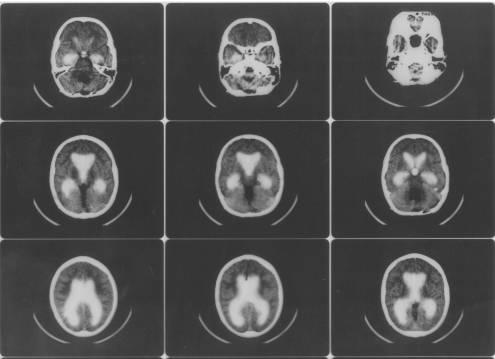

Комп'ютерна томографія (КТ) - у наш

час КТ займає домінуюче положення серед методів діагностики гідроцефалії. Це

технічно складний, але безпечний, надійний і безболісний спосіб діагностики

гідроцефалії. Пучок рентгенівських променів проходить крізь тіло пацієнта, а

зображення внутрішніх органів (у даному випадку мозку) створюються комп’ютером.

Саме дослідження займає від 5 до 10 хвилин. Ш,ь)